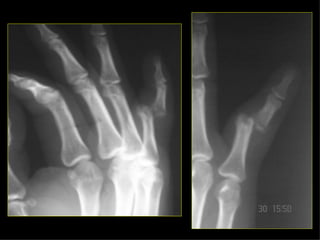

HOMBRO BRAZO CODO ANTEBRAZO MUÑECA MANO Monteggia Colles Fx escafoides

HOMBRO BRAZO CODOANTEBRAZO MUÑECA MANO Monteggia Colles Fx escafoides